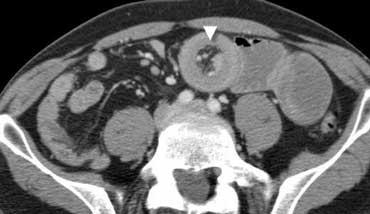

Khí trong ổ phúc mạc ở bệnh nhân nghi ngờ viêm ruột thừa. Khí được nhìn thấy rõ hơn trên hình ảnh với cửa sổ phổi ở bên phải.

Khí tự do

Sự hiện diện của khí tự do trong ổ phúc mạc là bằng chứng của thủng tạng rỗng, và là chỉ định cấp cứu ngoại khoa.

Tràn khí phúc mạc chỉ có hai nguyên nhân thường gặp:

– Thủng ổ loét dạ dày

– Thủng túi thừa đại tràng

Khí tự do thường không gặp trong viêm ruột thừa thủng.

Luôn khảo sát hình ảnh ở cửa sổ phổi để phát hiện khí tự do trong ổ bụng tốt hơn (hình minh họa).